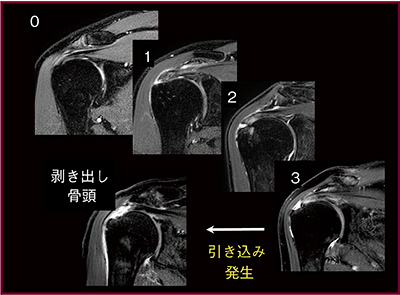

●腱板断裂ではなく剥離と考える

腱板断裂ではなく腱板剥離と考えることで,見えなかったものが見えてくることもある。上腕骨頭は回転したり,肩峰を突き上げたりすることでインピンジメントを生じる。筋と骨の接着剤である腱は,腱板停止付着部にストレスがかかることで剥がれることがあり,断裂よりも剥離と考えて読影する方が病変を見つけやすい。腱板剥離の観察では,大結節前方,棘上筋腱外側の最前縁に注目する。

全層断裂となって停止部を失うと,筋・腱の“引き込み”現象が生じる(図6)。引き込みが生じた筋萎縮を斜位矢状断だけで評価する場合は,過大評価に注意をする。

図6 引き込み現象